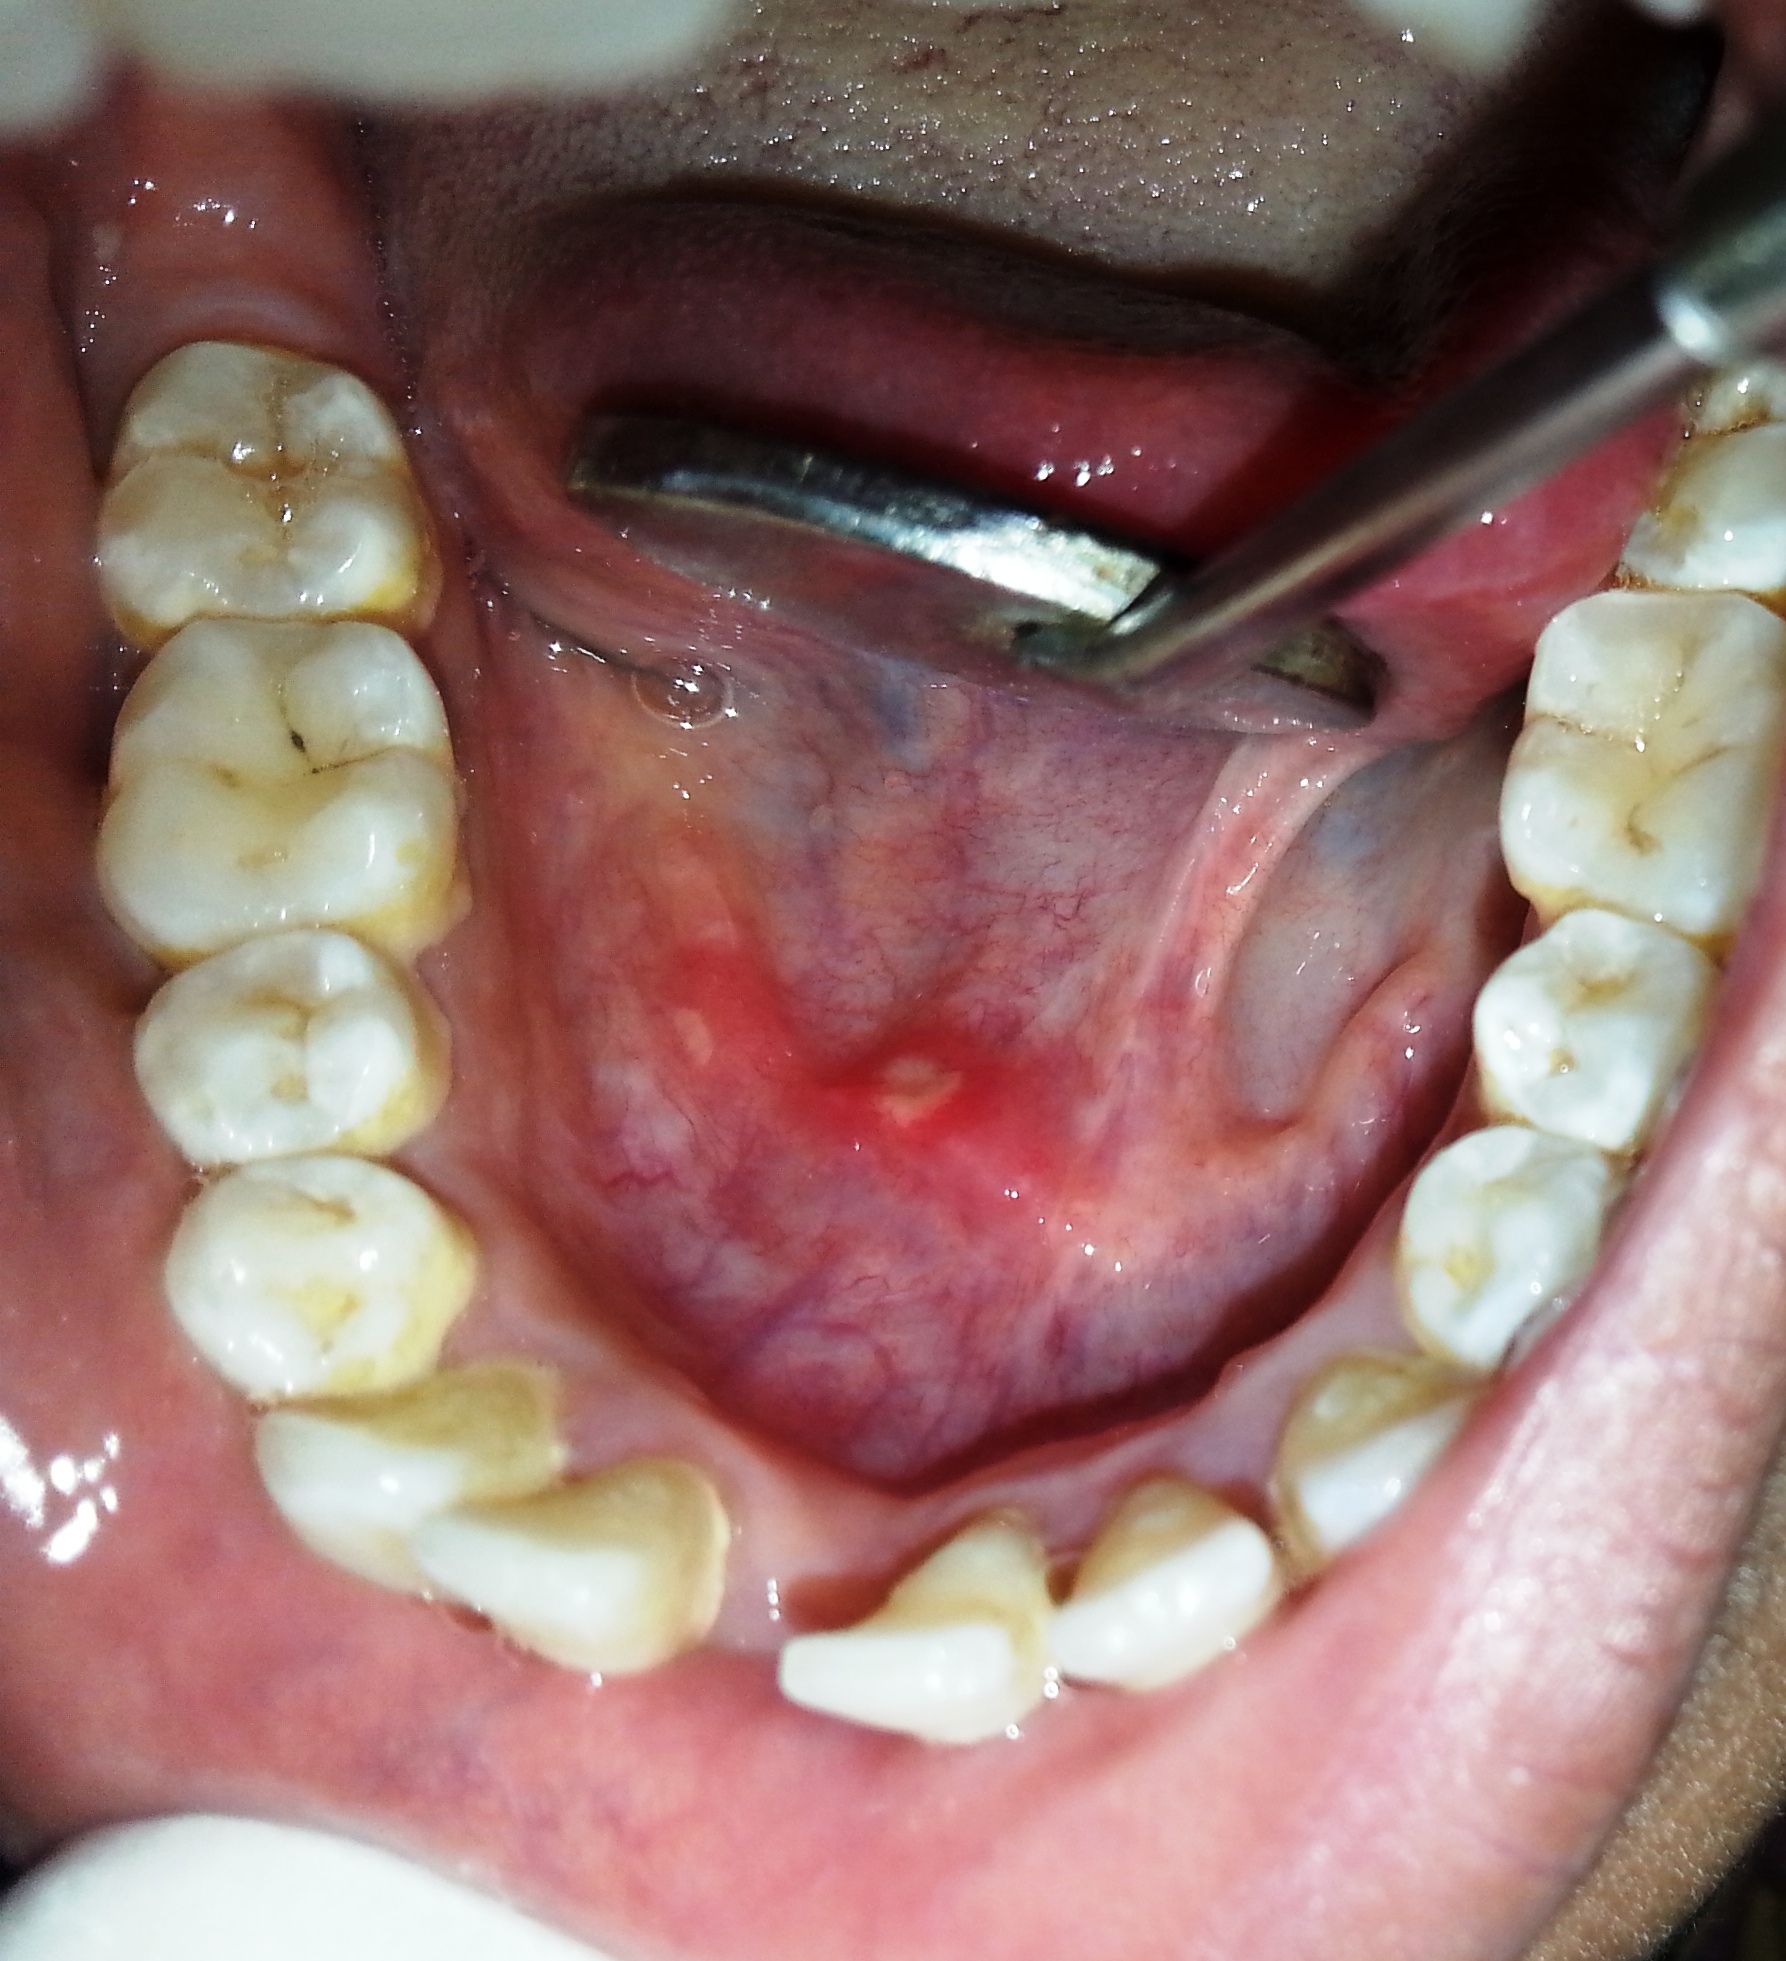

ORAL CANCER

The term "oral cancer" is used for any cancer that develops in tissues of the mouth (known as the oral cavity)..

ORA PRECANCER

Oral precancers are usually asymptomatic and painless so the patient is unaware of the lesions presence.

OROMUCOSAL

OROMUCOSAL OromucosalPreparations comply with the requirements of the European Pharmacopoeia.

aphthous ulcers